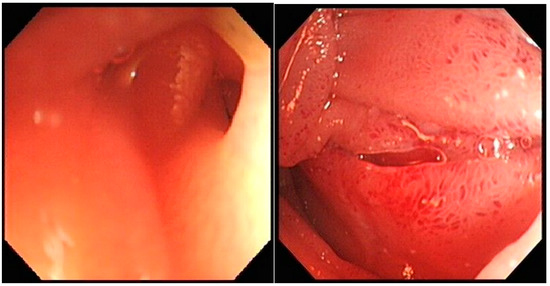

Repeat inpatient OGD was challenging as there was extrinsic compression in the area of third part of the duodenum (D3), preventing further passage of the endoscope, Figure 1.

Figure 1.

OGD images showing partial obstruction in the third part of the duodenum (D3) preventing the passage of the endoscope.